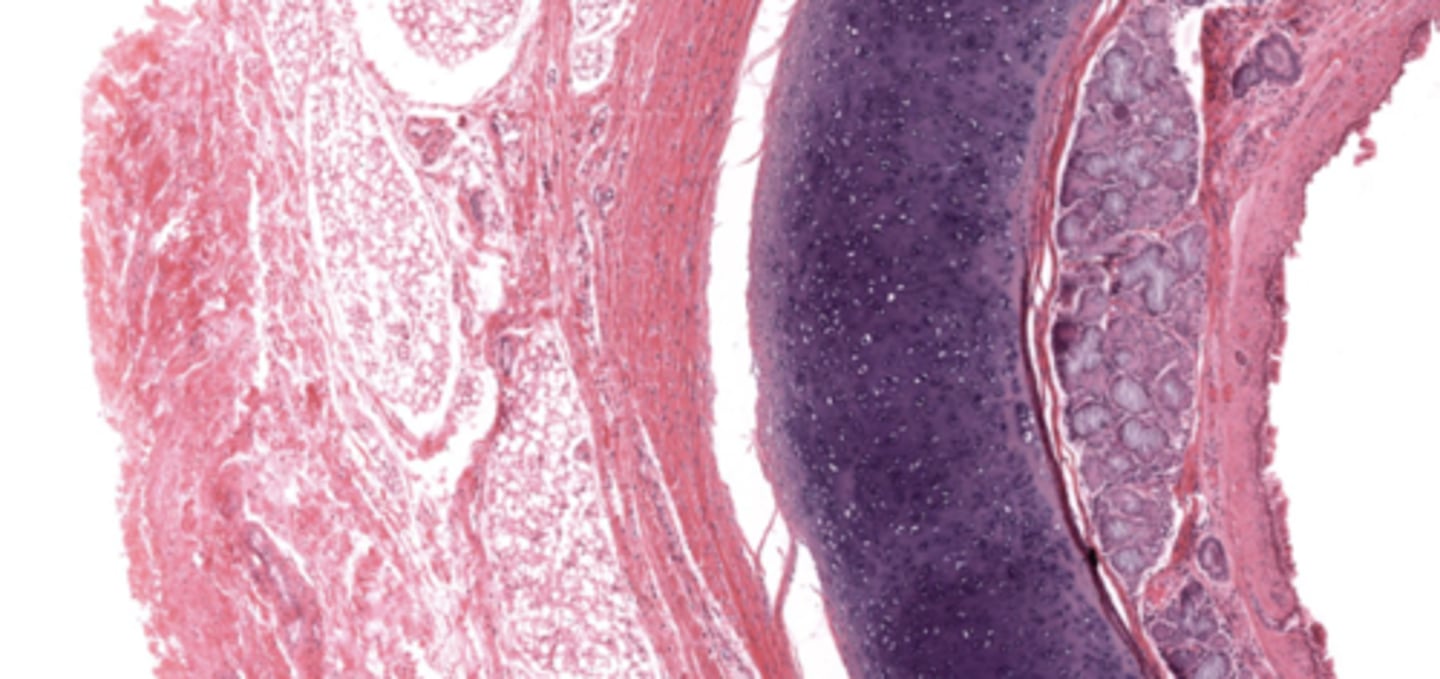

trachea

tracheal cartilage

respiratory epithelium